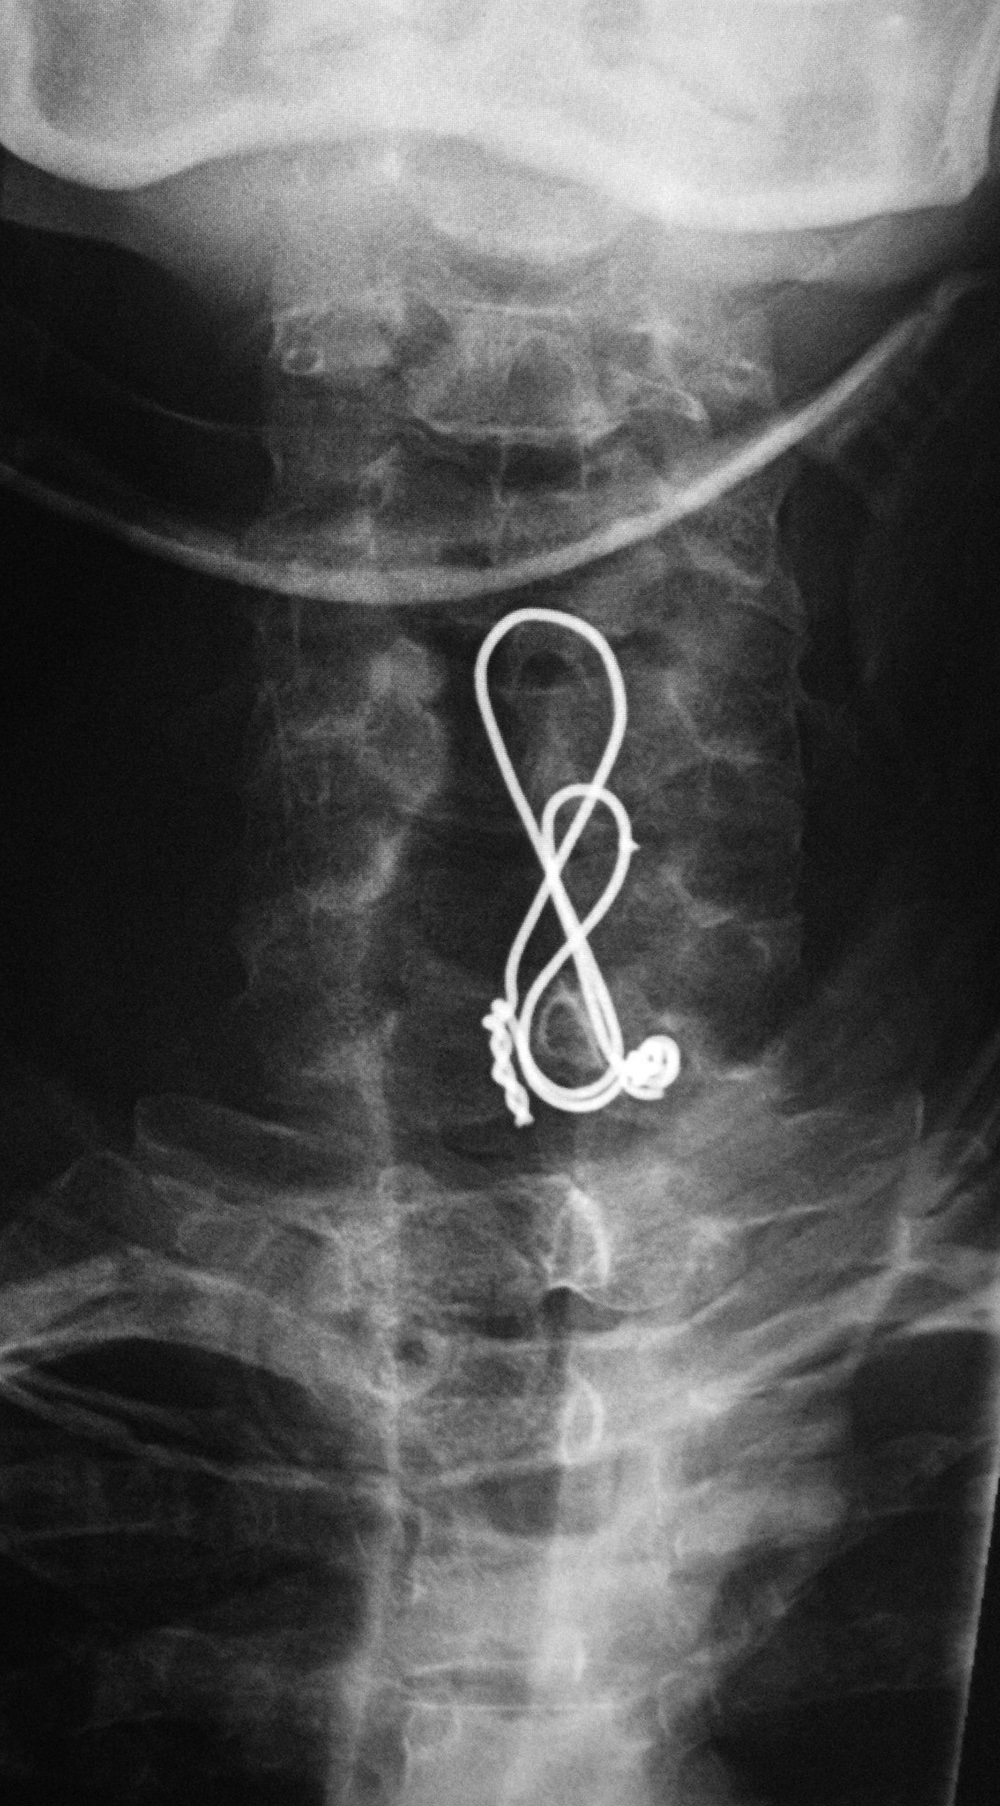

Posterior cervical wire figure of 8 construction - AP view |

Posterior cervical wire figure of 8 construction - lateral view |

44 year-old man with C7 vertebral fracture. Posterior figure of 8 wire fixation extends from C4 to C7 |